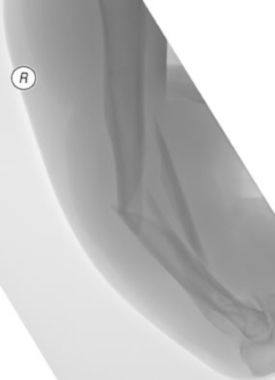

Comminuted complex humerus fracture